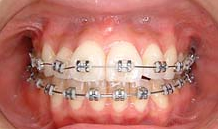

正面から観たところです。

全て乳歯です。反対咬合です。まだ幼児なので、お子様にかかる負担などをよく考えた上で、治療します。

反対咬合です。